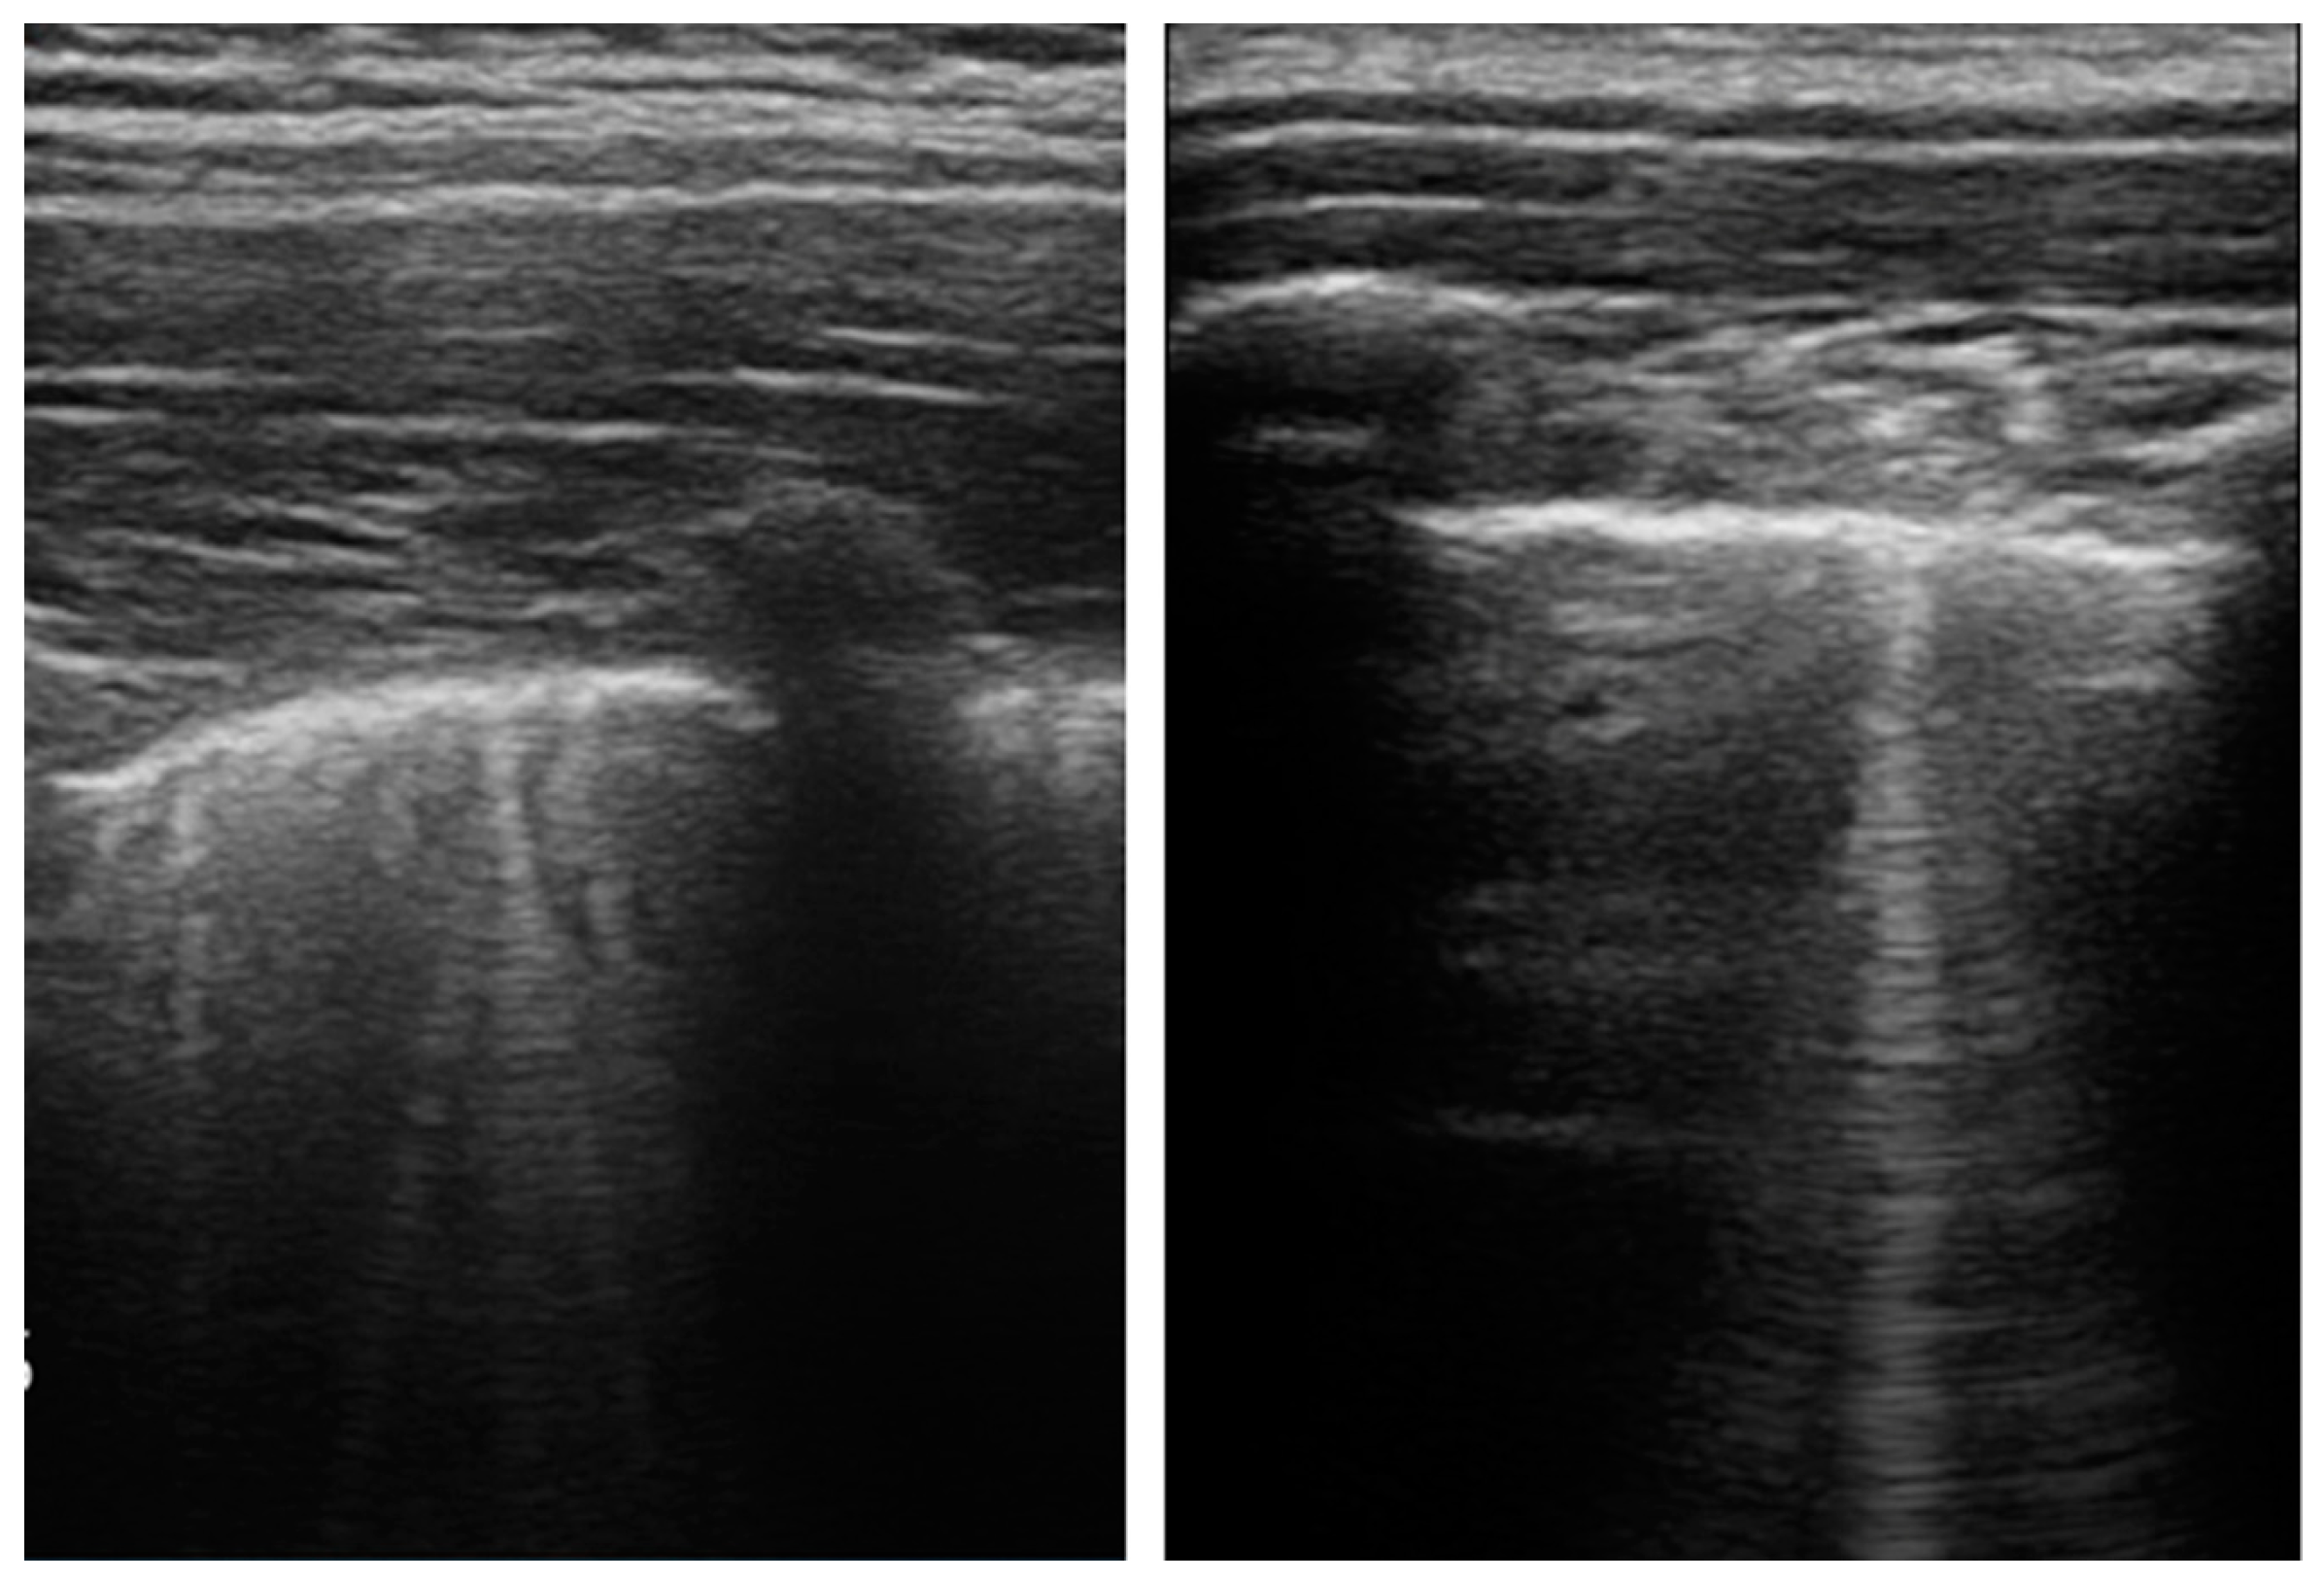

| B-Lines, n (%) | 15 (60.00) | 25 (89.29) | 0.003 |

| Several, non-coalescent B-Lines, n (%) | 3 (10.71) | 13 (46.43) | 0.003 |

| Several, coalescent B-Lines (white lung), n (%) | 2 (7.14) | 7 (25.00) | 0.07 |